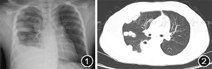

入院后检查:血液:白细胞计数17.19×109/L,中性粒细胞计数14.96×109/L,血红蛋白134 g/L,血小板计数244×109/L,C反应蛋白34.71 mg/L,红细胞沉降率100 mm/1 h。尿液:尿蛋白(±)。肝、肾功能正常。心电图示窦性心动过速。胸X线检查:右肺内高密度影,右侧肋膈角变钝(图1)。胸部CT:双侧肺野内多发结节状、斑片状密度增高影,右肺为著,部分病变内示气泡影,右侧胸膜多发局限性增厚,右侧胸腔内示液性密度影(图2)。查真菌G试验<10 ng/L。行CT引导下经皮肺组织穿刺活检术,术中抽出大量脓性分泌物。穿刺分泌物涂片镜检示:奴卡菌(图3)。病理示:纤维、横纹肌组织呈慢性化脓性炎(图4)。颅脑磁共振(MR):未见明显异常。